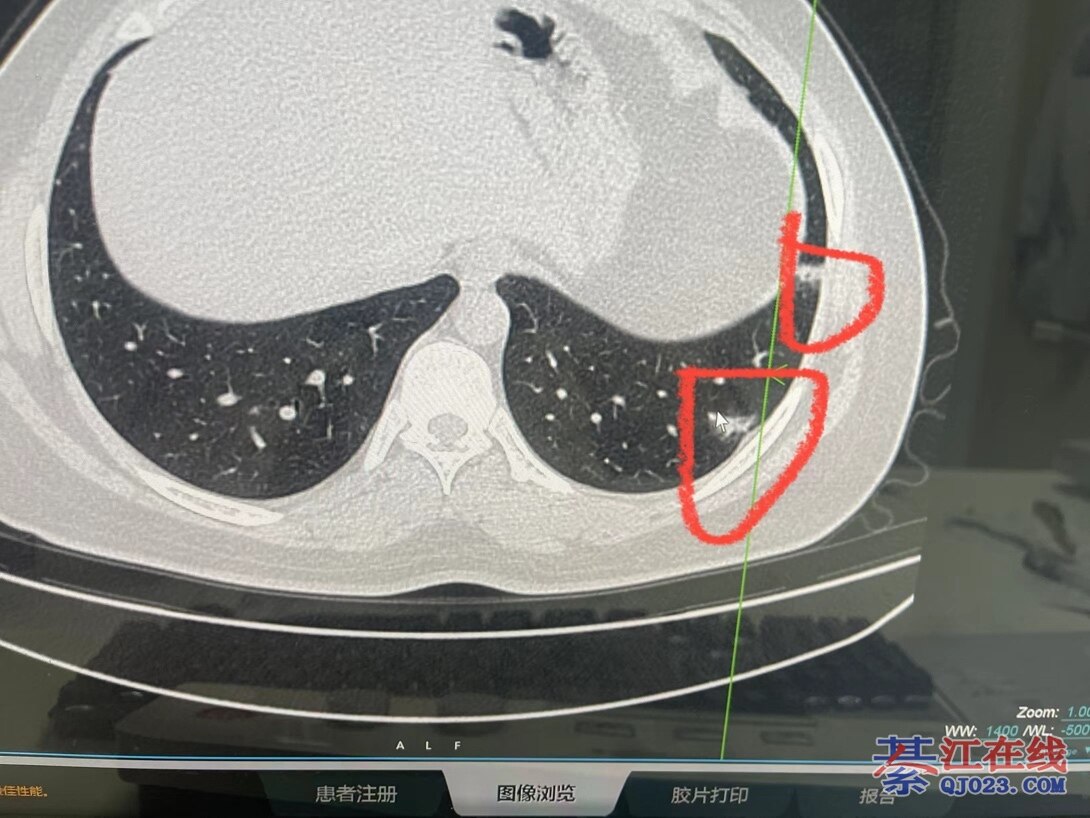

信了楼主的话,今天去做了CT,右肺中叶磨玻璃影,符合新冠病毒肺炎表现。阳了13天,症状早已消失,但是肺上还是有问题。

楼主应当注意的一点是, 阳康了,还是伴有剧烈咳嗽,并发胸痛呼吸困难这种, 实打实的身体非常不舒服了, 这种需要去医院做个CT看看,不是每个人都需要这样

,只是友情提醒大家一下

谢谢,因为身边有人现在没症状了,却检查出双肺感染,所以才好心提醒大家。信就信,不信就算了!不管别人怎么说我